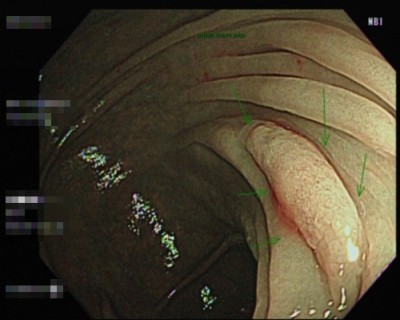

日前有30~39歲年齡層發生個案,分別為34歲莊小姐及38歲王先生兩位到北投健康管理醫院進行NBI無痛大腸內視鏡檢查,透過高端影像可清楚看見兩位體內已暗藏有高風險癌變的腺瘤,也在當次檢查中將息肉切除,免除了該息肉在日後發展成大腸癌的可能。

有大腸癌危險因子的年輕族群,千萬不可掉以輕心

日前有30~39歲年齡層發生個案,分別為34歲莊小姐及38歲王先生兩位到北投健康管理醫院進行NBI無痛大腸內視鏡檢查,透過高端影像可清楚看見兩位體內已暗藏有高風險癌變的腺瘤,也在當次檢查中將息肉切除,免除了該息肉在日後發展成大腸癌的可能。

【個案說明】

莊小姐,34歲,在腸壁皺摺處發現鋸齒狀腺瘤息肉(綠色箭頭處),大小約1.2 公分。屬於大腸直腸腺癌的癌前病變,鋸齒狀腺瘤息肉經常分布於近端大腸,外型通常較為扁平,且邊緣模糊,容易被糞水與黏液覆蓋於表面,因此有時在內視鏡下不容易被發現,需仔細觀察。